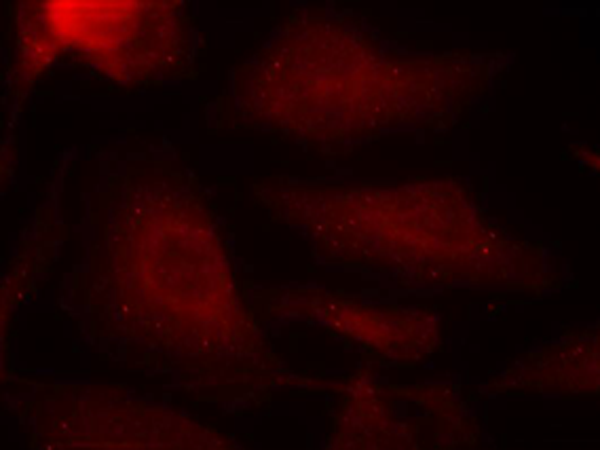

IF Positive control:

Hela cells

IF Recommended dilution

100-200